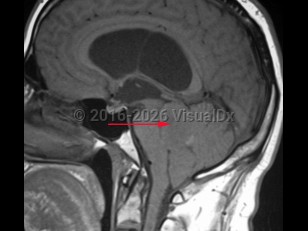

EpendymomaEpendymoma

NeurocysticercosisNeurocysticercosis

Subarachnoid hemorrhageSubarachnoid hemorrhage

Carcinomatous meningitis